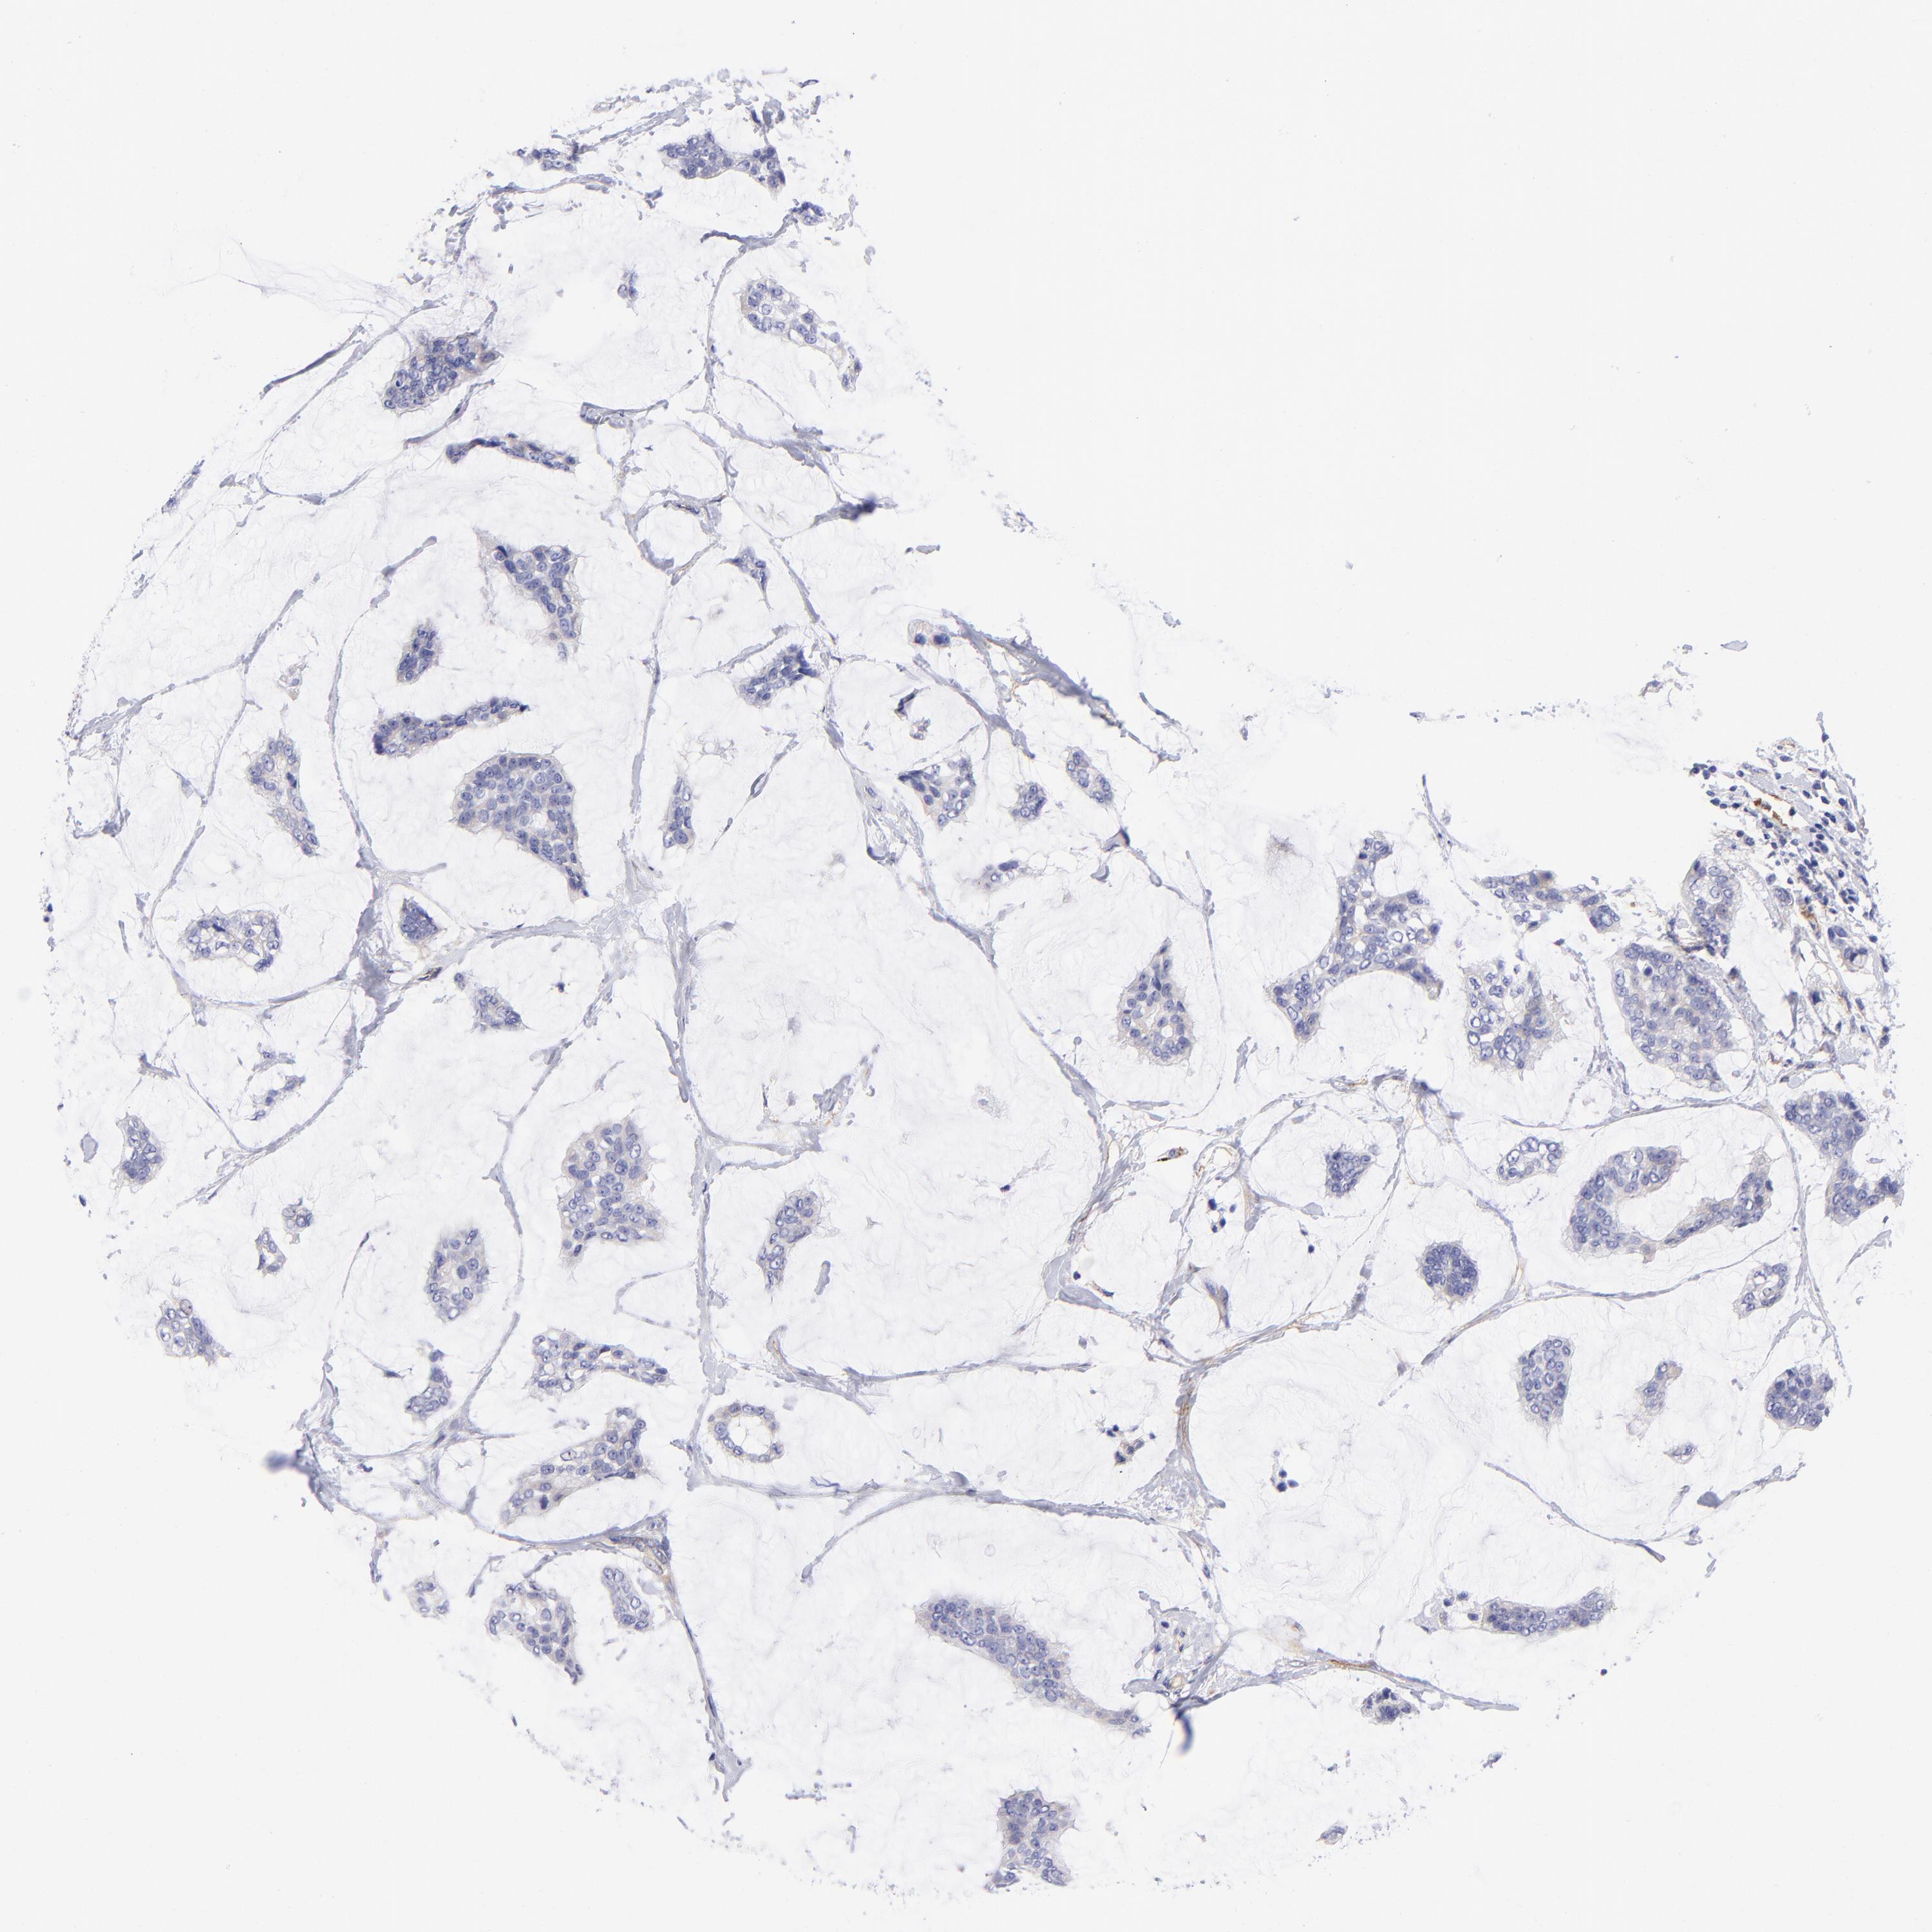

BRCA TCGA BRCA VALIDATION PROTEIN EXPRESSION